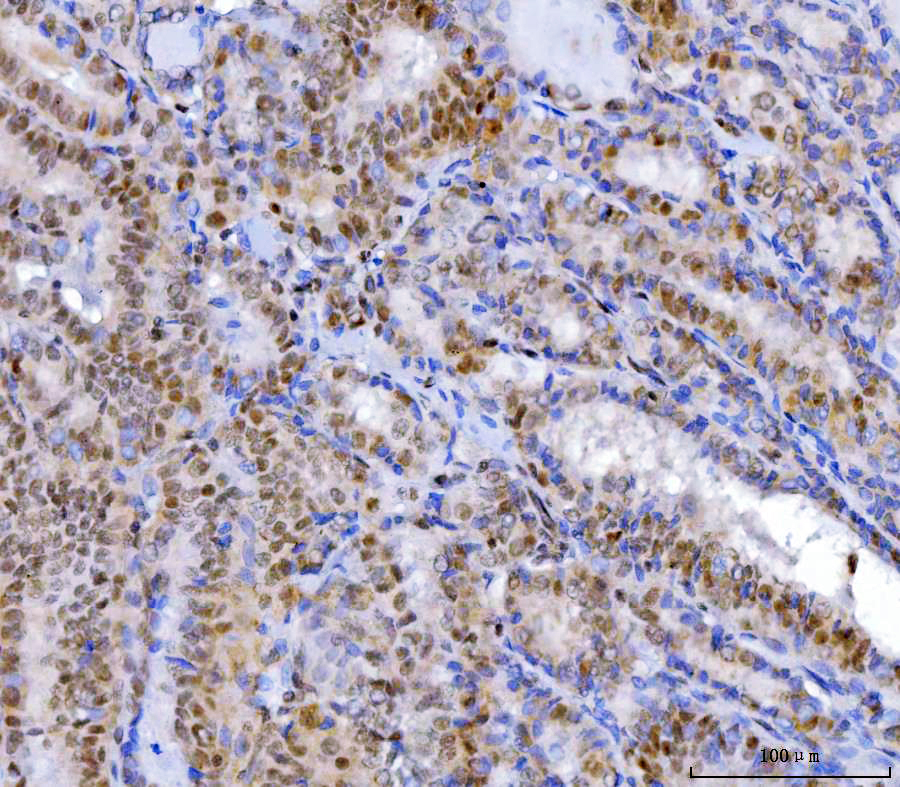

IHC analysis of YY1 using anti-YY1 antibody (M00833-2).

YY1 was detected in a paraffin-embedded section of human thyroid cancer tissue. The tissue section was incubated with mouse anti-YY1 Antibody (M00833-2) at a dilution of 1:200 and developed using HRP Conjugated mouse IgG Super Vision Assay Kit (Catalog # SV0001) with DAB (Catalog # AR1027) as the chromogen.